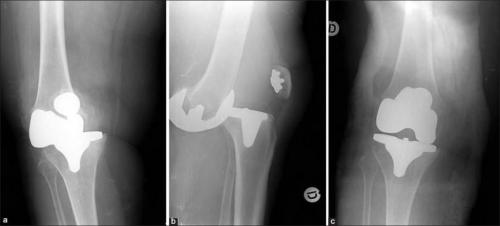

Такое может случиться, если очень торопиться. Это вывих коленного импланта.